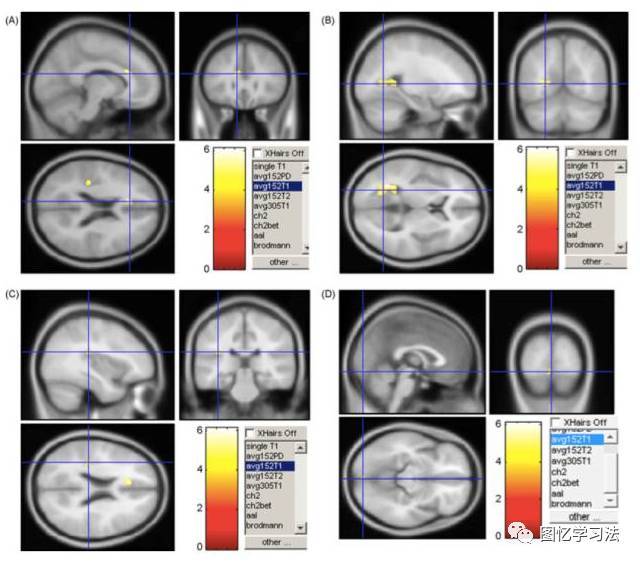

越来越多的证据表明,网络成瘾会使大脑灰质的体积减少。上海交通大学和中国科学院的研究人员发现,网络成瘾青少年的大脑存在结构性改变。通过对比18名网络成瘾青少年与15名健康青少年的大脑成像结果,他们发现,“网瘾”青少年在某些大脑区域的灰质密度显著低于对照组,其中包括与成瘾密切相关的脑岛和控制情绪的扣带回(见图二)。

图二 网瘾青少年的大脑灰质密度在(A)左前扣带回皮层、(B)左后扣带回皮层、(C)左侧脑岛和(D)左舌回显著低于对照组青少年